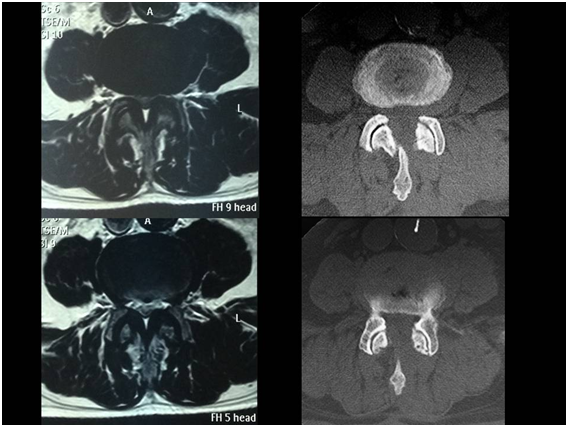

All the patients were assessed with dynamic lumbar X-rays and MRI of the lumbo-sacral spine. Patients with more than Grade II spondylolisthesis (Meyerding grading scale), mobile listhesis as shown in dynamic X-rays, spondylolysis, multisegmental narrow canals, facet synovial cysts and patients with a history of lumbar spine surgery were excluded. Thirteen male and seventeen female patients underwent surgery. Mean age was 66.7 yrs. (47-84); median age, 73. Levels L4-L5 (20), L3-L4 (6) y L5-S1 (4) were surgically managed (Figure 1).

Figure 1 case 1:  78 yrs old male presenting claudication at 50 meters. The MRI shows narrowing in the L3-L4 segment.  MED was performed and the clinical symptoms resolved.

Figure 4 Control MRI and CT scan of the patient in Figure 1.